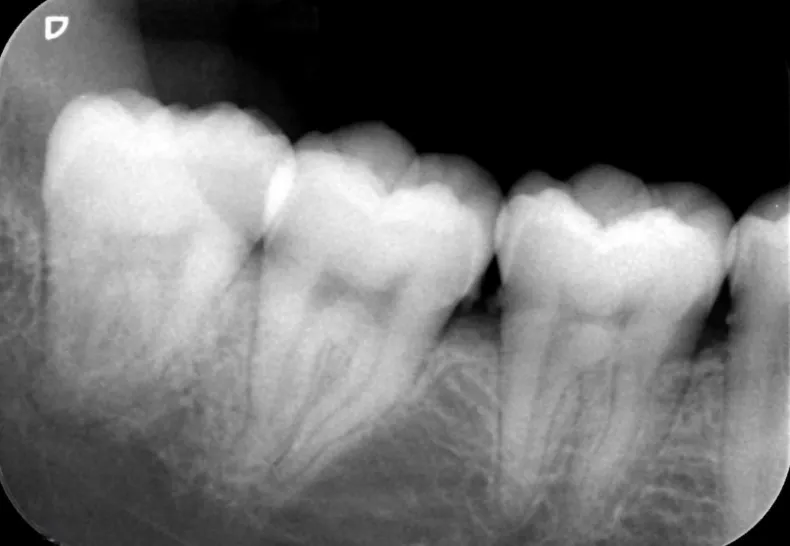

レントゲン検査

歯周病によって歯槽骨がどれくらい失われたか、本来の高さからどの程度減ってしまったかレントゲン検査で確認します。また、顎や副鼻腔といった周辺組織の状態も調べられます。